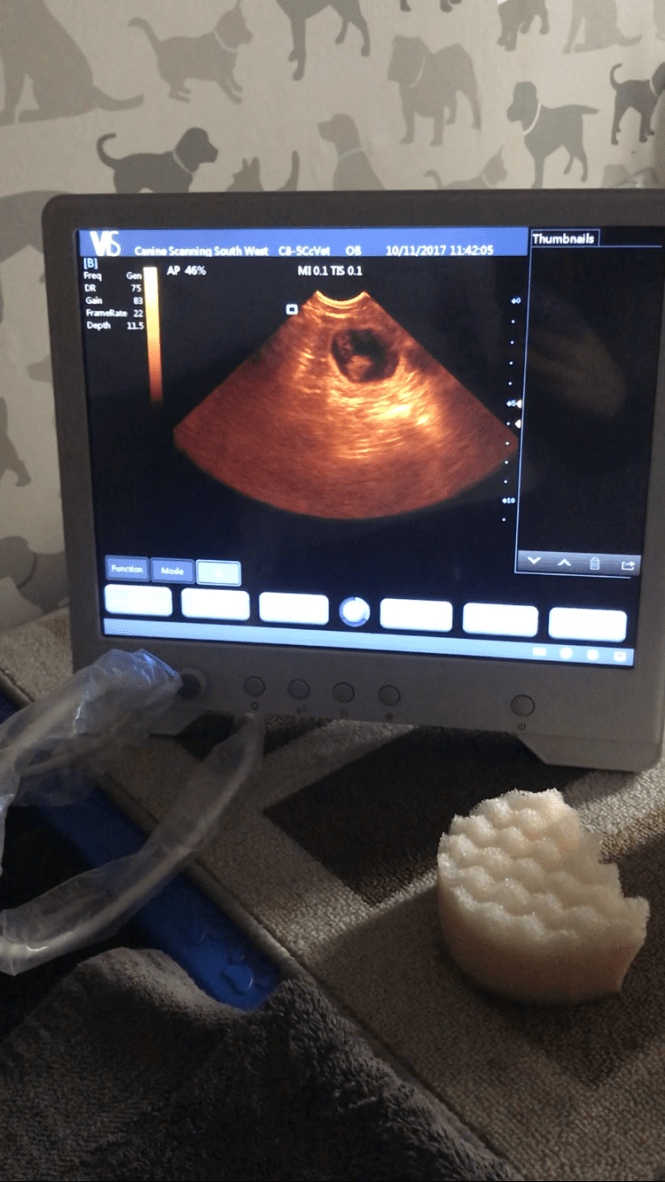

Pregnancy confirmed! November 10, 2017November 10, 2017avonwolf Leave a comment We are happy to announce that the little D’s are on the way and look healthy😃. We scanned Lucy today and there are definitely puppies in there👌🏻🍾🥂. For more updates check out the puppy diary click Share this: Share on X (Opens in new window) X Share on Facebook (Opens in new window) Facebook Like Loading... Related